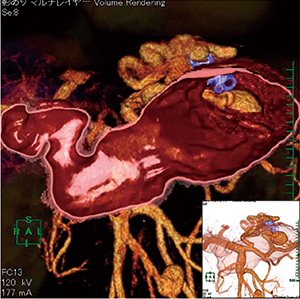

心房細動カテーテルアブレーション(シミュレーション)(図4)と胆嚢腫瘍(隆起型)(図5)に応用した画像を示す。

図4 仮想内視鏡応用例1 |

図5 仮想内視鏡応用例2 |